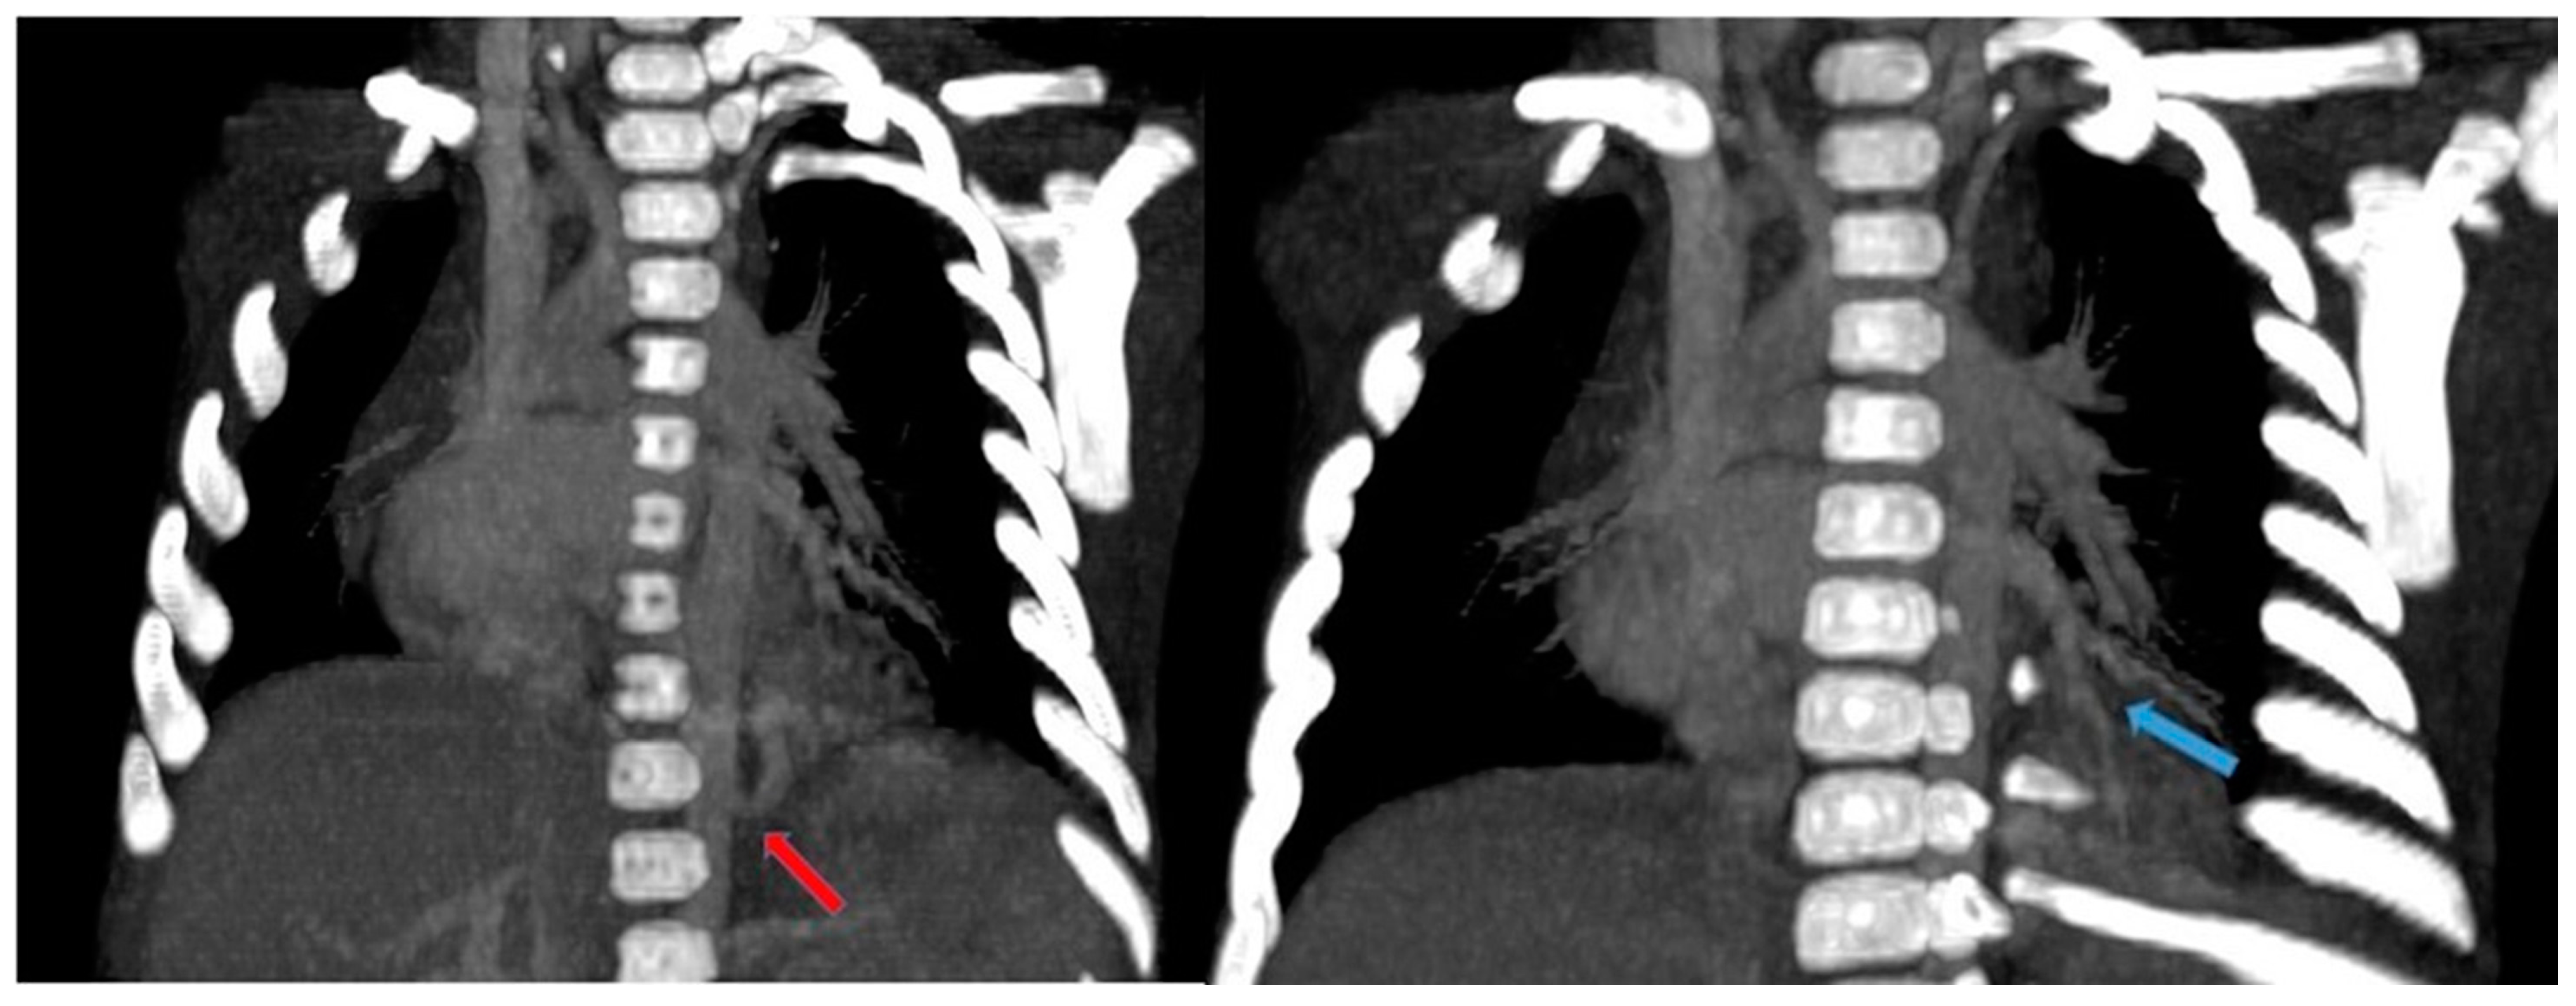

CT angiography with 3D reconstruction serves as a highly informative tool for identifying anomalous feeding arteries and drainage veins for differentiating between intra- and extra-lobar sequestration (Figure 14 and Figure 15). The CT appearance of the lesion ranges from a homogeneous soft tissue mass within the parenchyma (Figure 16) to a cystic lesion containing air or fluid, which can coexist in hybrid forms [15,37].

Figure 14.

CT angiography with maximum intensity projection (MIP) reconstruction shows an anomalous artery (red arrow) arising from left gastric artery (LGA) into sequestered lung and an anomalous vein (blue arrow) draining into inferior vena cava, in its intrahepatic tract. These findings are compatible with extra-lobar sequestration.

Figure 15.

CT angiography with maximum intensity projection (MIP) reconstruction shows an anomalous artery (red arrow) arising from abdominal aorta and coursing toward the sequestered lung and an anomalous vein (blue arrow) draining into the pulmonary venous system. These findings are compatible with intra-lobar sequestration.